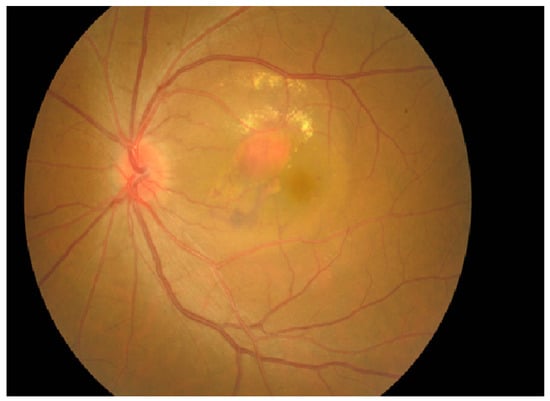

4.2. Fundus Photography

- Chaikitmongkol, V.; Khunsongkiet, P.; Patikulsila, D.; Ratanasukon, M.; Watanachai, N.; Jumroendararasame, C.; Mayerle, C.B.; Han, I.C.; Chen, C.J.; Winaikosol, P.; et al. Color Fundus Photography, Optical Coherence Tomography, and Fluorescein Angiography in Diagnosing Polypoidal Choroidal Vasculopathy. Am. J. Ophthalmol. 2018, 192, 77–83. [Google Scholar] [CrossRef]

- Chaikitmongkol, V.; Kong, J.; Khunsongkiet, P.; Patikulsila, D.; Sachdeva, M.; Chavengsaksongkram, P.; Dejkriengkraikul, C.; Winaikosol, P.; Choovuthayakorn, J.; Watanachai, N.; et al. Sensitivity and Specificity of Potential Diagnostic Features Detected Using Fundus Photography, Optical Coherence Tomography, and Fluorescein Angiography for Polypoidal Choroidal Vasculopathy. JAMA Ophthalmol. 2019, 137, 661–667. [Google Scholar] [CrossRef]